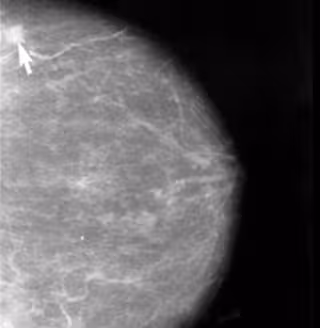

Las células inmunes juegan un papel clave en la metástasis temprana del cáncer de mama

Cáncer de Mama

Las células inmunes que se alojan en los conductos de la leche del tejido mamario, llamadas macrófagos, juegan un papel clave en la metástasis temprana del cáncer de mama, según un estudio llevado a cabo por expertos del Instituto del Cáncer Tisch en la Escuela de Medicina Icahn en Mount Sinai de Nueva York (Estados Unidos) y que ha sido publicado en la revista 'Nature Communications'.

El estudio, realizado en ratones y con células humanas, ha puesto de manifiesto que la metástasis se origina cuando los macrófagos son atraídos por los conductos de la leche, desencadenando una reacción en cadena que permite que las células cancerosas se diseminen a otras partes del cuerpo.